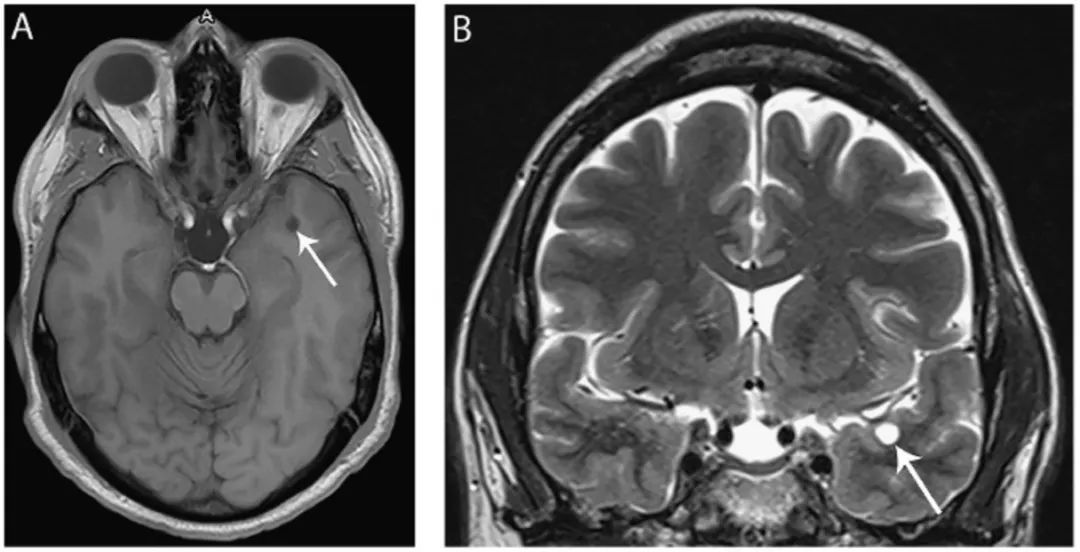

图3 脉络膜裂神经上皮囊肿

(A) 冠状位T2WI显示位于海马区上方,起源于脉络膜裂的囊肿(箭头);(B)FLAIR像显示同一囊肿(箭头)位于中脑外侧、颞叶内侧。

图4 小神经胶质囊肿

(A) 轴位T1WI像和冠状位T2WI像(B)显示左侧颞叶前方边界清晰的实质内囊肿(箭头),等CSF信号。